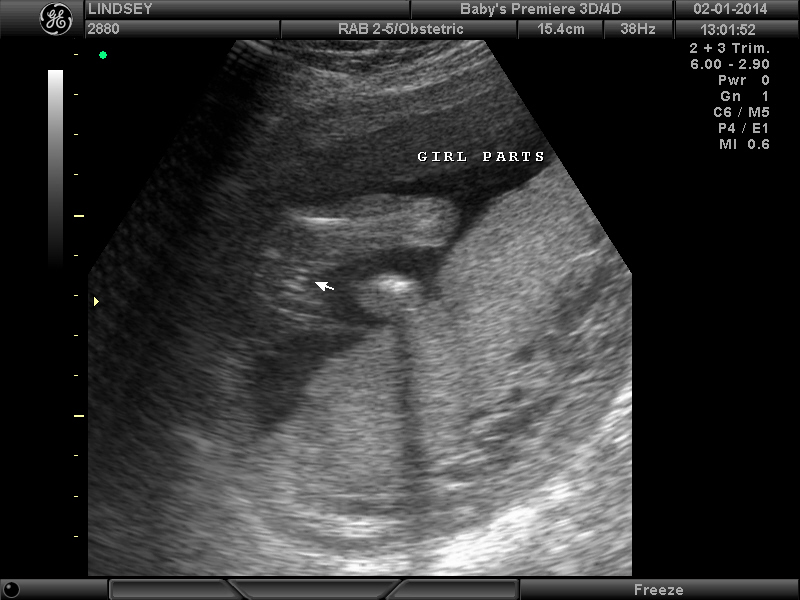

3 Attachment(s)

Help confirming 'girl' ultrasound??

So my Dr. was making me wait a while longer to find out the gender but since I was sooo impatient we went for an elective ultrasound this weekend at 18 weeks. The tech said she was sure it's a girl (yay!!) but I'm so nervous to 100% trust it because I still can't make much sense of the ultrasound myself despite her pointing parts out. (Sorry, new at this! :worry:) It just seems so hard to tell what angle she's seeing everything at. Can anyone ease my my mind and confirm that these are in fact girl parts?? I need to buy something pink!Thanks for any help!! :) :DD: Attachment 16772Attachment 16773Attachment 16774